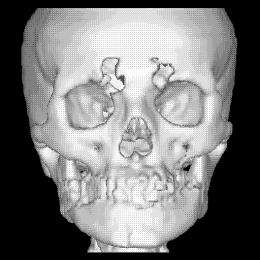

La figura 1‑9 mostra un esempio di surface rendering. Si noti come grazie all’ombreggiatura si avverte la sensazione di tridimensionalità.

Figura 19 Ricostruzione 3D in surface rendering